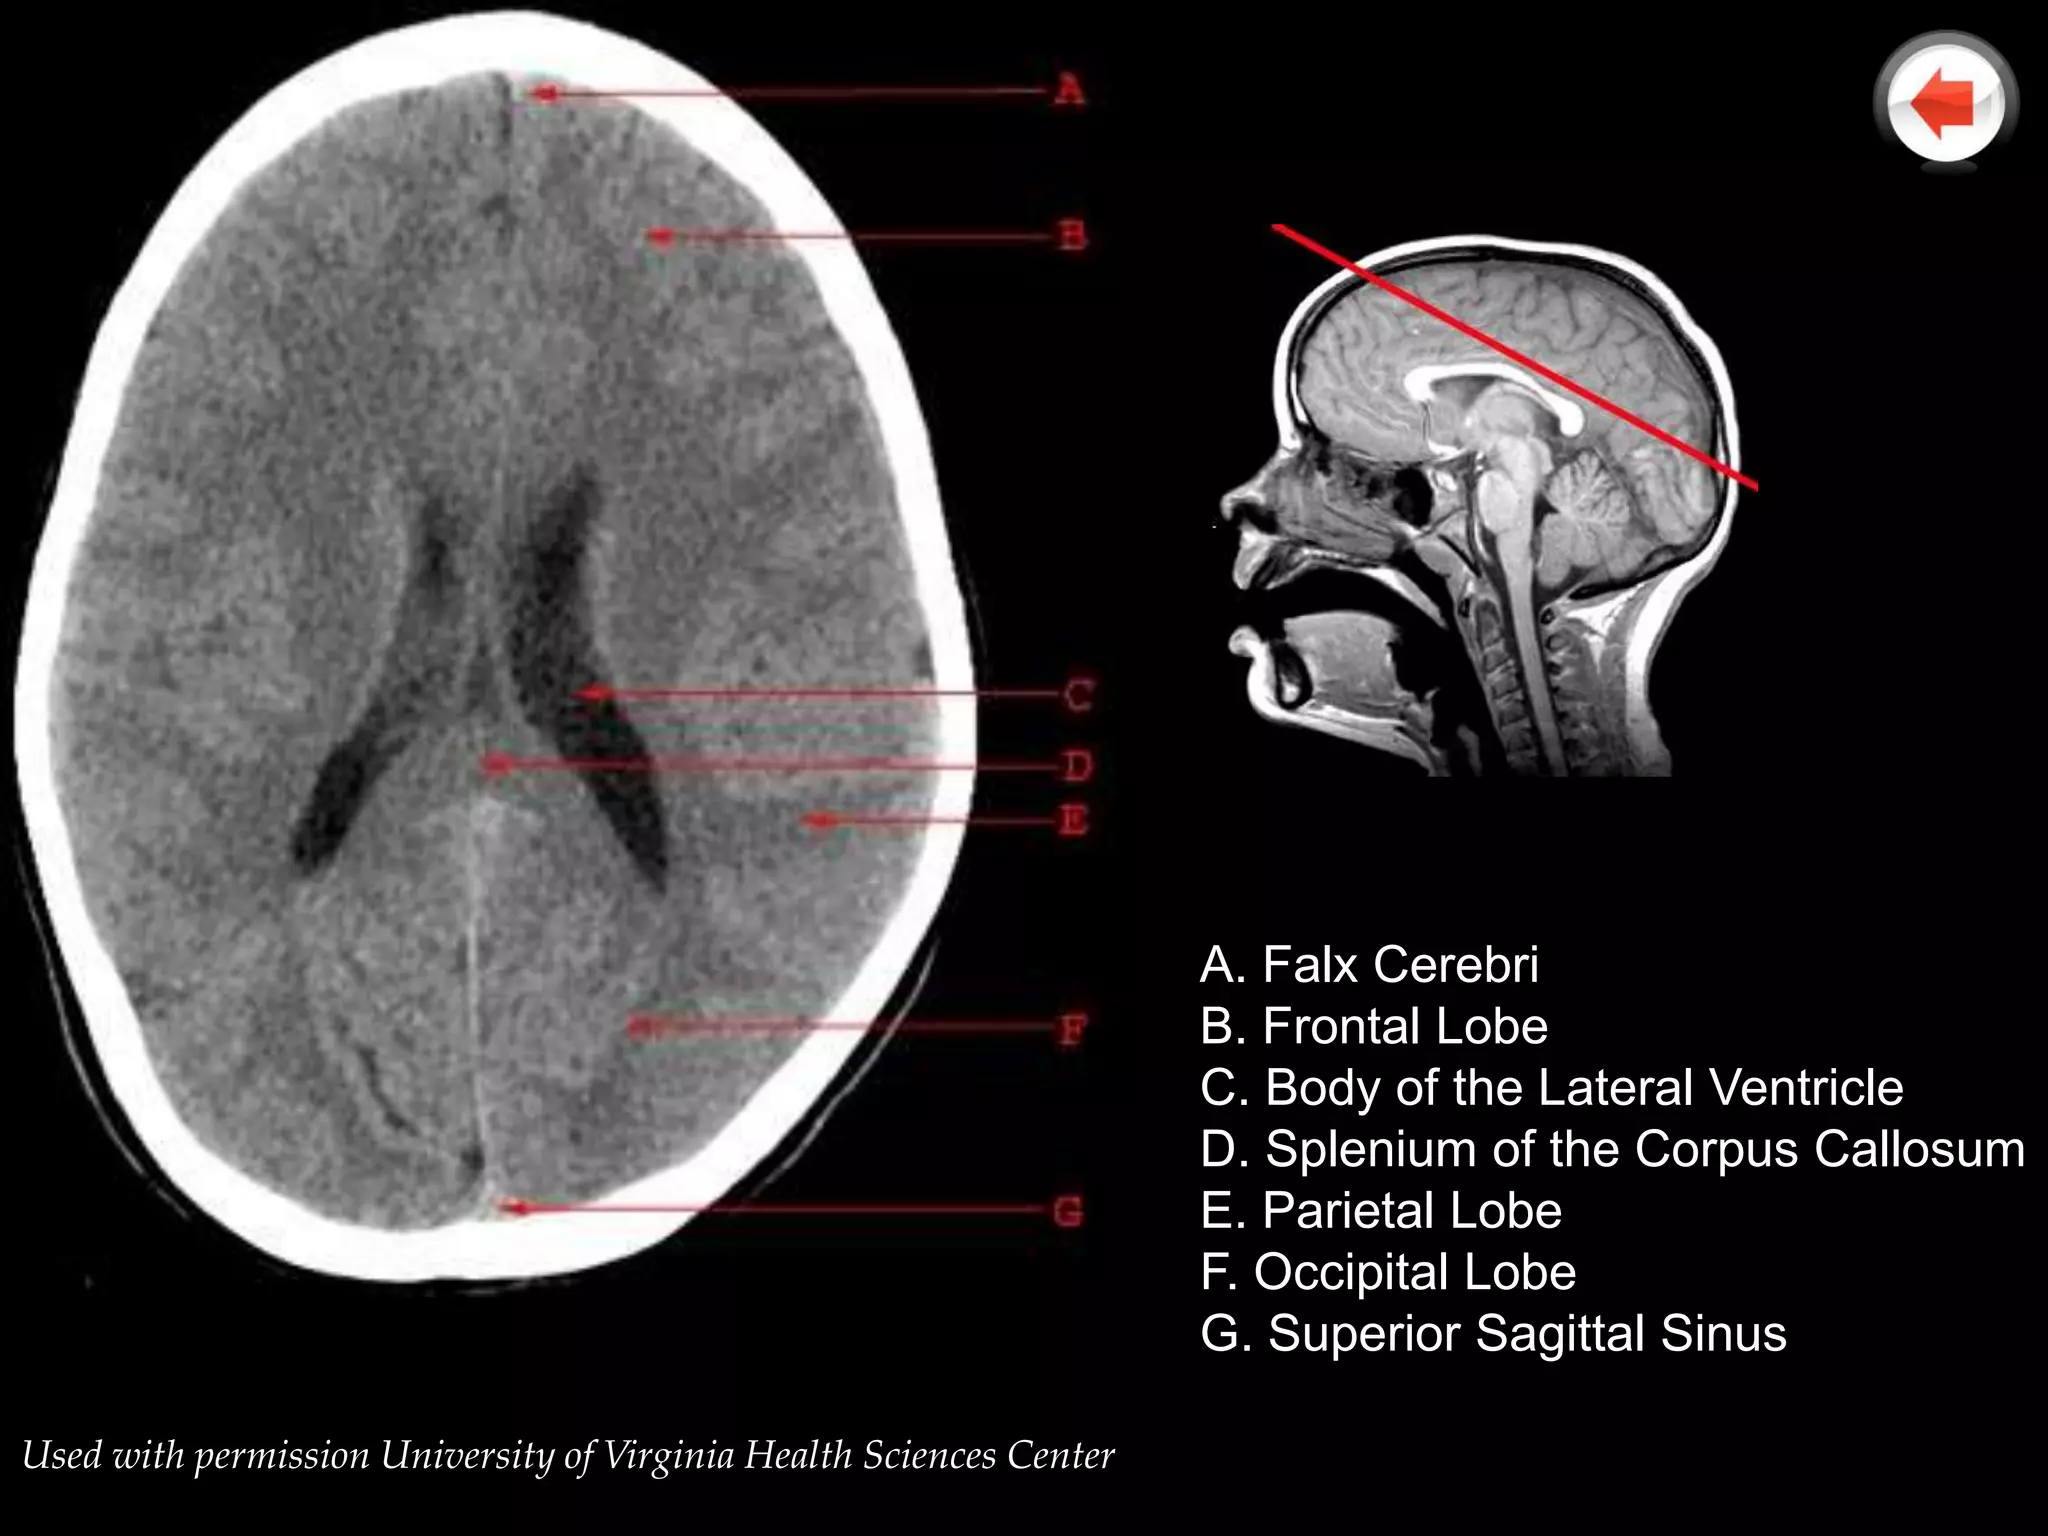

A. Falx Cerebri

B. Frontal Lobe

C. Body of the Lateral Ventricle

D. Splenium of the Corpus Callosum

E. Parietal Lobe

F. Occipital Lobe

G. Superior Sagittal Sinus

Used with permission University of Virginia Health Sciences Center